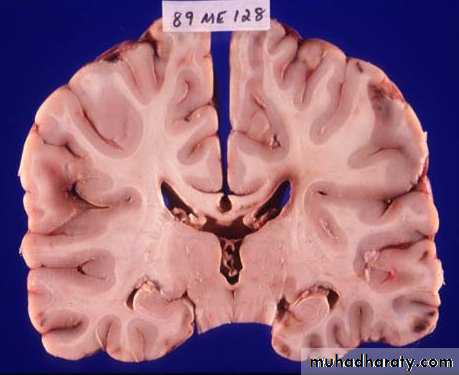

1. Diffuse Axonal Injury

Prolonged post-traumatic state in which there is loss of consciousness from the time of injury that continues beyond 6 hours.Occurs as a result of mechanical shearing at the grey-white matter interface.

This causes disruption and tearing of axons, myelin sheaths and blood capillaries.

Severity can range from mild damage with confusion to coma and even death.